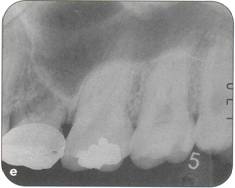

Fi 545e45f g 5-8ee Six weeks after transplantation. Fi 545e45f g 5-8ff Clinical view 6 weeks after trans plantation |

Fi 545e45f g 5-8gg Three months after transplantation. Inflammatory root resorption is ob. served on the distal aspect of the donor tooth. Root canal therapy was started immediately. Fi 545e45f g 5-8hh One month after temporary obturation with calcium hydroxide. Arrest of root resorption was confirmed and orthodontic treatment was started. |